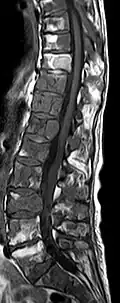

Magnetresonanztomografie

Mit der Magnetresonanztomografie (MRT) können insbesondere Weichteilgewebe gut bildmäßig dargestellt werden. Sie gilt für die Diagnostik von spinalen Metastasen (Metastasen in der Wirbelsäule) als Goldstandard. Mit der MRT können darüber hinaus weitere Komplikationen im Bereich der spinalen Metastasen, wie beispielsweise Infektionen oder Verletzungen des Bandscheiben- und Ligamentkomplexes, Knochenmarködeme nach einer frischen Fraktur,[117][118] oder Kompressionen neuraler Strukturen, sichtbar gemacht werden.[18]:16 Mit Hilfe der STIR-Sequenz (engl. short tau inversion recovery) ist es möglich, das Alter einer Fraktur zu ermitteln. Zum Aufspüren von Metastasen ist die T1-Wichtung mit Gadolinium-haltigen Kontrastmitteln, wie beispielsweise Gadotersäure, besonders gut geeignet. Das Kontrastmittel reichert sich in den Metastasen besonders stark an.[18][119]

- Vergleich CT / MRT bei osteolytischen Metastasen eines Mammakarzinoms in der Wirbelsäule

Sagittale native T1-gewichtete MRT -

Sagittale native T1-gewichtete MRT. Deutlich sichtbar die Ausdehnung bis in die Bogenwurzeln.